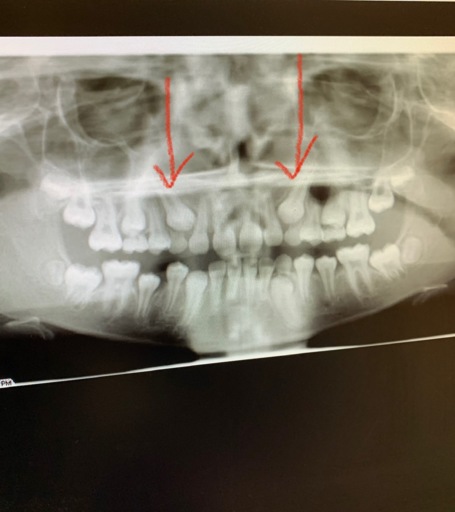

What shall i do with case complain from bone loss and gummy smile ?

case 26 old come to my clinic complain from her smile , after diagnosis is completed Patient suffer from gingival recession with bone loss in upper and lower arch , gingival dept in limited area was 4 , patient had bad history of orthodontic treatment with extraction of 2 upper canines and malaligment of teeth , she complain from pulmonary problems and mouth breather with v shape arch What shall i do in this case